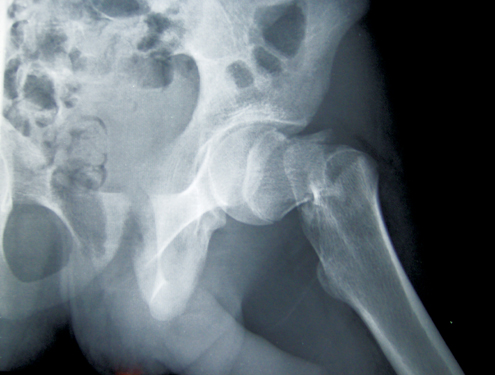

A osteoporose é uma doença crônica, mais comum em idosos, que coloca as pessoas em maior risco de sofrer uma fratura óssea. “Mais preocupantes são as fraturas da coluna vertebral e do quadril que podem resultar em incapacidade em longo prazo, perda de independência e até morte precoce”, alerta o especialista.